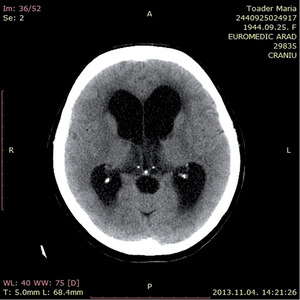

3.6.1. Hydrocephalus (59–63. ábra)

- Koponya-CT: kamrák mérete– frontalis kamraszarv/belső koponya átmérő,temporalis kamraszarvak nagysága,periventricularis liquorkilépés jele,külső liquorterek komprimáltsága.